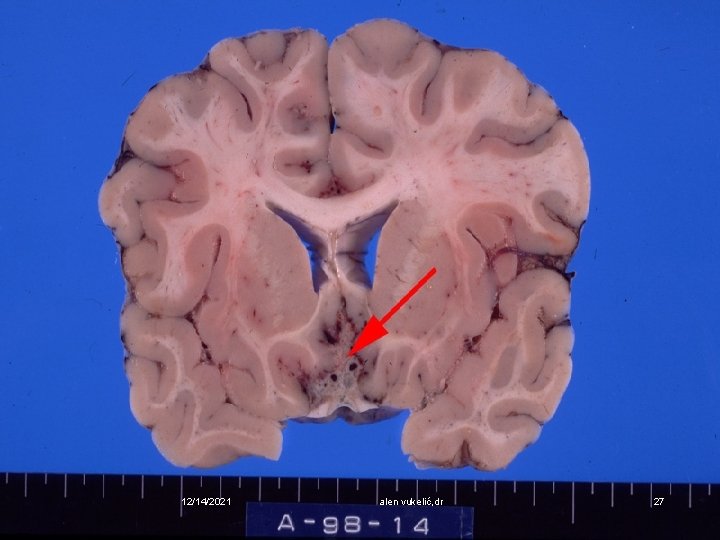

v Postprimarna tuberkuloza nastaje endogenom reaktivacijom primarnog žarišta v To je eksudativna pneumonija s kazeoznom nekrozom i stvaranjem kaverni 12/14/2021 alen vukelić, dr 21